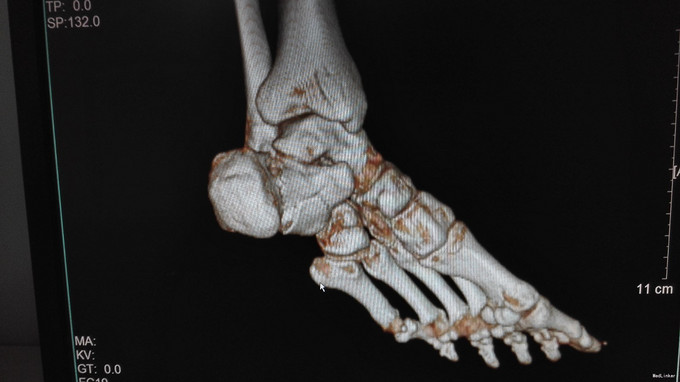

左足跟淤血肿胀明显,无明显畸形,皮肤完整,局部压痛明显,可扪及骨擦感,纵向叩击痛阳性,足趾活动正常,末梢血运、感觉正常。左跟骨X片示:左跟骨粉碎性骨折,左足部CT示:左侧跟骨粉碎性骨折,累及跟距关节面。

左跟骨粉碎性骨折,排除手术禁忌症后行左跟骨粉碎性骨折切开复位内固定术。

中年男性患者,因“跌倒致左足跟部疼痛、活动受限4小时”入院,左跟骨X片及左足部CT提示:左跟骨粉碎性骨折,累及跟距关节面。结合临床症状、体征及影像学检查,诊断左跟骨粉碎性骨折,且累及关节面,手术指征明确,排除手术禁忌后行切开复位内固定术,术后复查X片示对位良好。出院1月后复查,1月内避免负重。